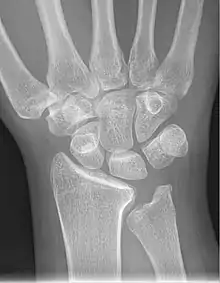

Left hand x-ray with Kienbock's Disease showing 4 mm negative ulnar variance and Kienbock's Disease Stage IIIB